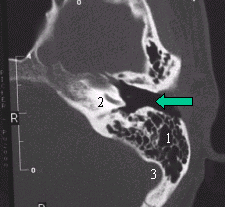

TAC corte frontal

Vemos el CAE libre (flecha verde) y continua la zona desgastada (flecha blanca) de la cortical mastoidea.

TAC corte horizontal

Conducto libre (flecha verde) 1-Cavidad mastoidea ventilada 2-Coclea – Corte en su sector inferior 3-Seno lateral |